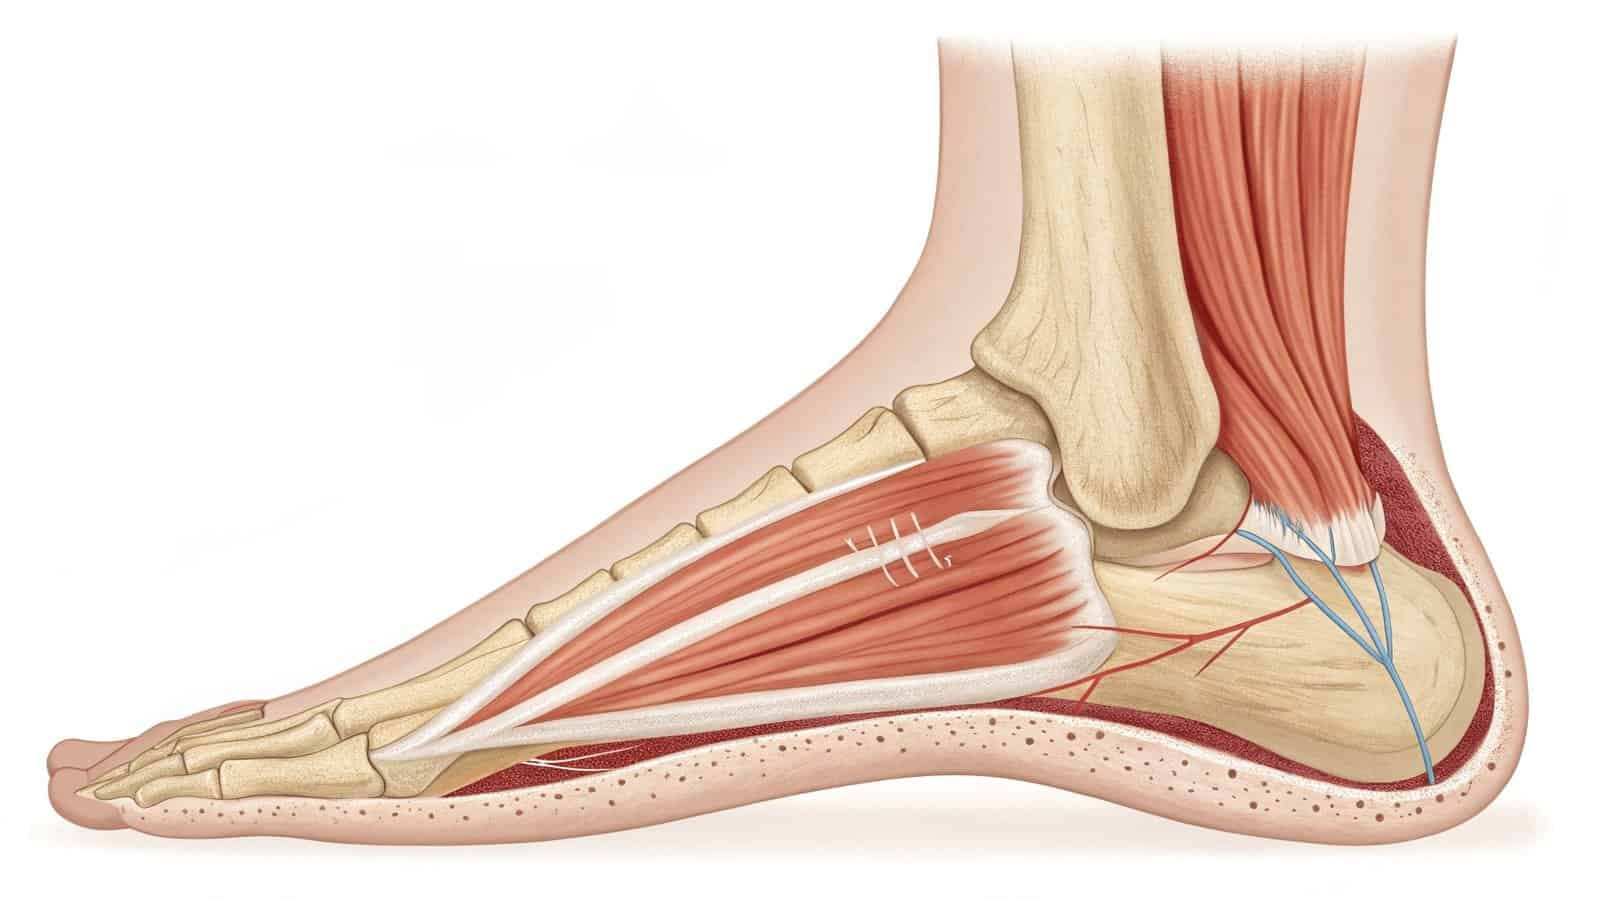

Plantar fasciitis occurs when the thick band of tissue connecting your heel to toes becomes inflamed. Proper treatment combines rest, stretching, and targeted therapy to promote healing and prevent recurrence.

The plantar fascia absorbs shock during movement. Overuse, poor mechanics, or sudden increases in activity strain this tissue, causing microtears and inflammation at its weakest points.

Critical Stress Zones

The plantar fascia suffers most at these key locations:

1. Heel Attachment Point

- Bears maximum tension during push-off

2. Arch Region

- Collapsed arches overstretch the fascia

3. Forefoot Transition Zone

- Where fascia fibers fan out

- Tight Achilles tendons

The YD023’s unique design combines broad muscle relaxation with focused fascial treatment. First, the 16mm stroke prepares large calf muscles. Then, the precision head delivers 3D vibrations4 exactly where needed. This sequential approach mimics professional therapy protocols you’d receive in a clinic.